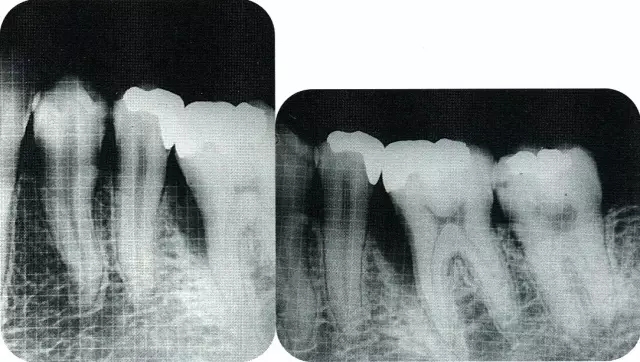

▲圖7-7  術(shù)前,術(shù)后的x片。確認(rèn)出現(xiàn)骨再生,牙槽嵴硬線。